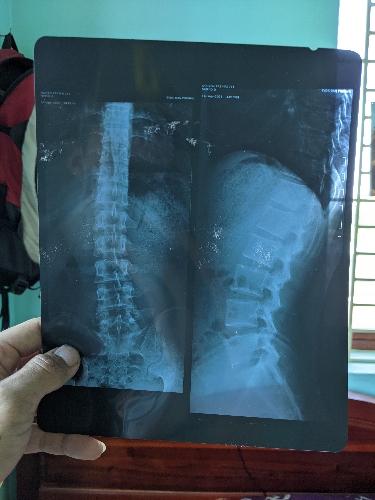

Chào bác sĩ, mấy hôm nay em có cảm giác tê ở vùng bìu tinh hoàn không đau, thi thoảng có cảm giác nhói vài lần rồi hết, khi em đi lại thì ko thấy cảm giác, chỉ khi ngồi em còn có cảm giác nhói ở phần xương mông ạ, cách đây nửa tháng em có đi khám ở pk nam khoa, kết quả siêu âm ,xét nhiệm của em đều ko có vấn đề gì, bác sĩ tư vấn tình trạng giúp em với ạ...em cảm ơn!